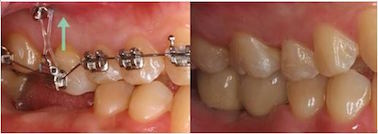

Q:迷你骨釘是什麼?

傳統的矯正治療常常以後牙、鄰近穩定的牙或是口外矯正裝置充當矯正錨定(不動的支撐點)來排列牙齒。然而有些病患牙齒缺失,牙齒因罹患牙周病支持組織不夠或是成年矯正病患不方便配戴口外矯正裝置,矯正的錨定不足會影響矯正的效果、時間與穩定性。目前臨床技術發展出將迷你骨釘放在牙床上,提供矯正時額外的錨定,提高了矯正的方便性與效果。

更多關於迷你骨釘的介紹,請閱讀 此篇文章